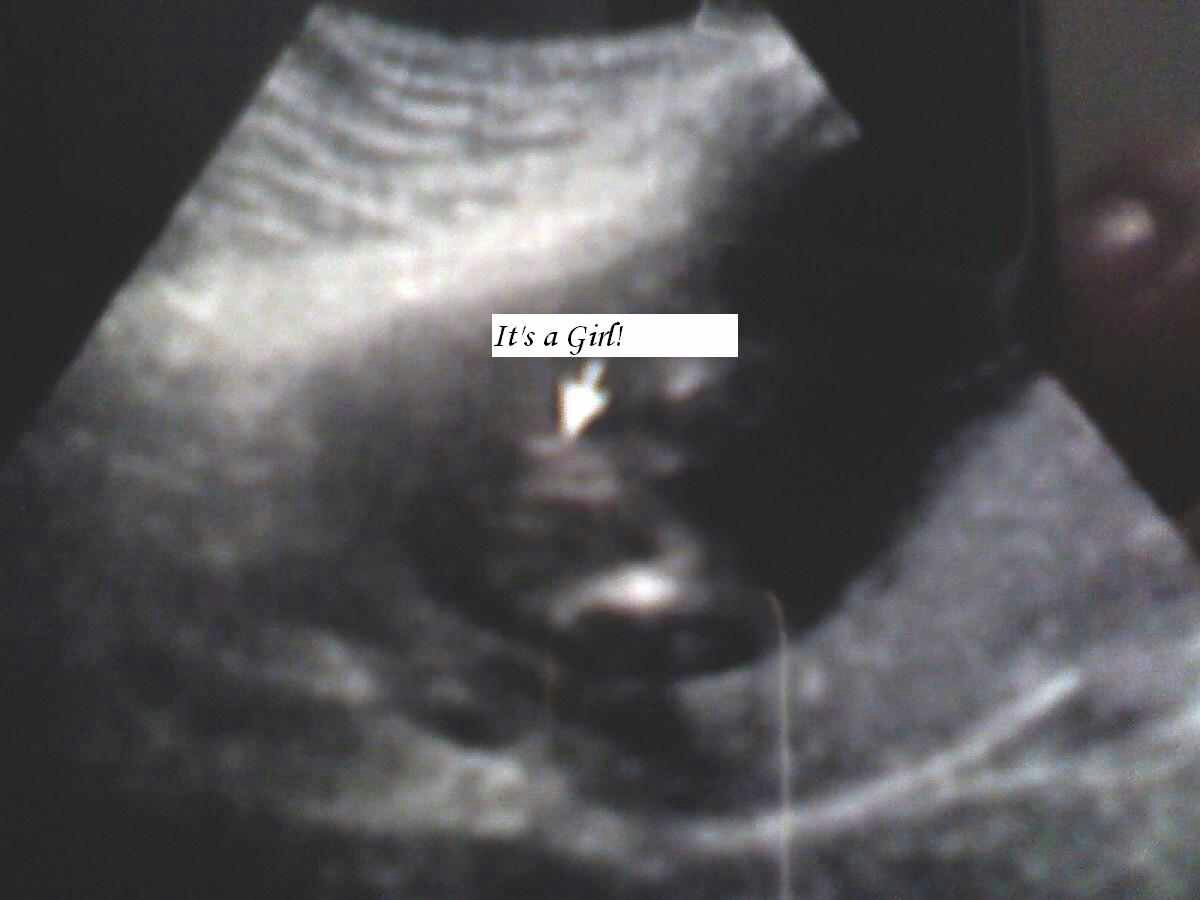

16w- definitely girl?

I had an early gender ultrasound done at 16w--- it shows girl.

The tech was super fast and didn't look at different angles. How sure should I be this is a girl? I'm nervous due to positioning (looks like from behind) and b/c its early. Im having. Gender reveal photoshoot this weekend & im nervous please help!

Yes, I think it's a girl. It has 3 lines.

The three lines look like a girl however, I am having a hard time orienting myself to the scan. I don't see legs like I would like to see?? It looks like there is a foot below the "girl bits"?

Thanks for replying! Its actually a hand/arm underneath. The legs are straight out if you look really hard you can see them :) the tech was very sure i think im just in denial because i thought boy for sure :)

I think i see the three lines! Im just in denial lol